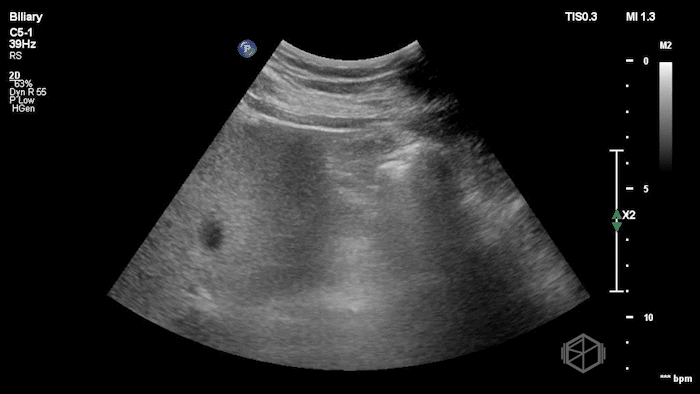

Their POCUS is below:

The POCUS demonstrated a thickened, edematous gallbladder wall with tumefactive sludge and gallstones, concerning for acute cholecystitis, though an underlying mass could not be excluded. A CT scan was obtained, which showed a layering gallstone versus gallbladder polyp, gallbladder wall edema, and possible pericholecystic fluid.

Surgery was consulted and recommended a radiology ultrasound, which predictably reported findings similar to the initial POCUS examination: gallbladder neoplasm versus tumefactive sludge versus non-calcified gallstones, with gallbladder wall edema concerning for acute cholecystitis. The radiology read recommended further evaluation with MRCP, which ultimately demonstrated findings consistent with acute cholecystitis without evidence of malignancy.

Diagnosis: Acute cholecystitis, tumefactive sludge